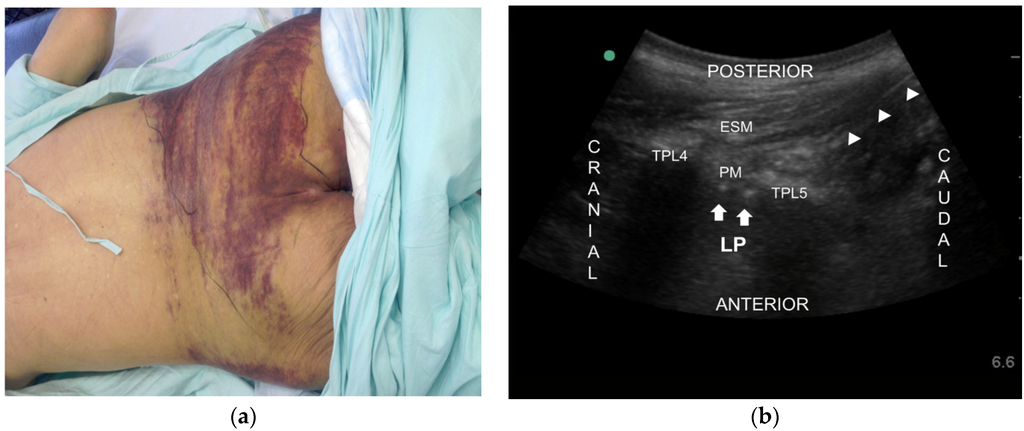

2.2. Case 2